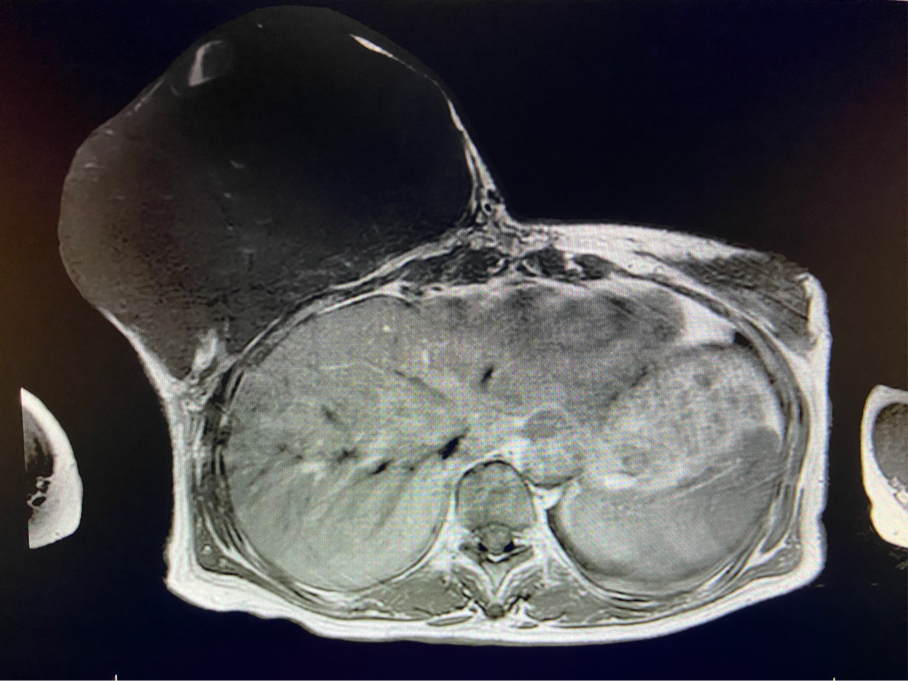

2周前,王女士的右乳外下方皮膚破潰,伴大量滲液,還發(fā)出陣陣惡臭。經(jīng)多方打聽,王女士從外地來到西安國(guó)際醫(yī)學(xué)中心醫(yī)院甲乳外科劉曉敏主任處就診。入院后,迅速完善了一系列相關(guān)術(shù)前檢查:王女士的雙乳外形不對(duì)稱,右乳約22?20cm,皮膚水腫明顯并可見靜脈曲張。右乳外下象限皮膚可見局部破潰,創(chuàng)面有3處,共約6?4cm大小,創(chuàng)面呈暗紅色,伴有血性滲出及惡臭,局部皮膚溫度升高。右側(cè)腋窩可觸及腫大淋巴結(jié)。

該患者右乳巨大腫物術(shù)前初步考慮乳腺葉狀腫瘤可能,因腫瘤太大,幾乎遍及整個(gè)右側(cè)乳房,為保證“無瘤原則”,術(shù)中切除范圍位置未知,極有可能出現(xiàn)皮瓣缺損。于是,經(jīng)過和整形醫(yī)院郭樹忠院長(zhǎng)、整形外科王愛武主任的討論,提供了兩種手術(shù)方式,一是創(chuàng)面修復(fù)(植皮或轉(zhuǎn)移皮瓣修復(fù)創(chuàng)面),二是乳房再造,與患者及家屬溝通后,決定先解決腫物,3年病情不再?gòu)?fù)發(fā)后,可以再考慮乳房重建。